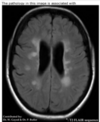

State where this stroke has occured

Right MCA